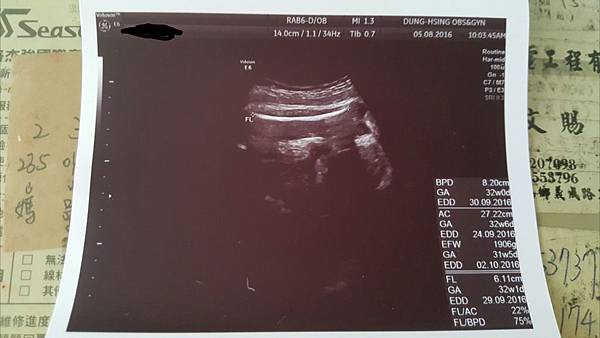

105.7.20更新

昨天去產檢確定是女兒了喔陰唇照的很清楚

這是陰唇喔非常清楚的特徵